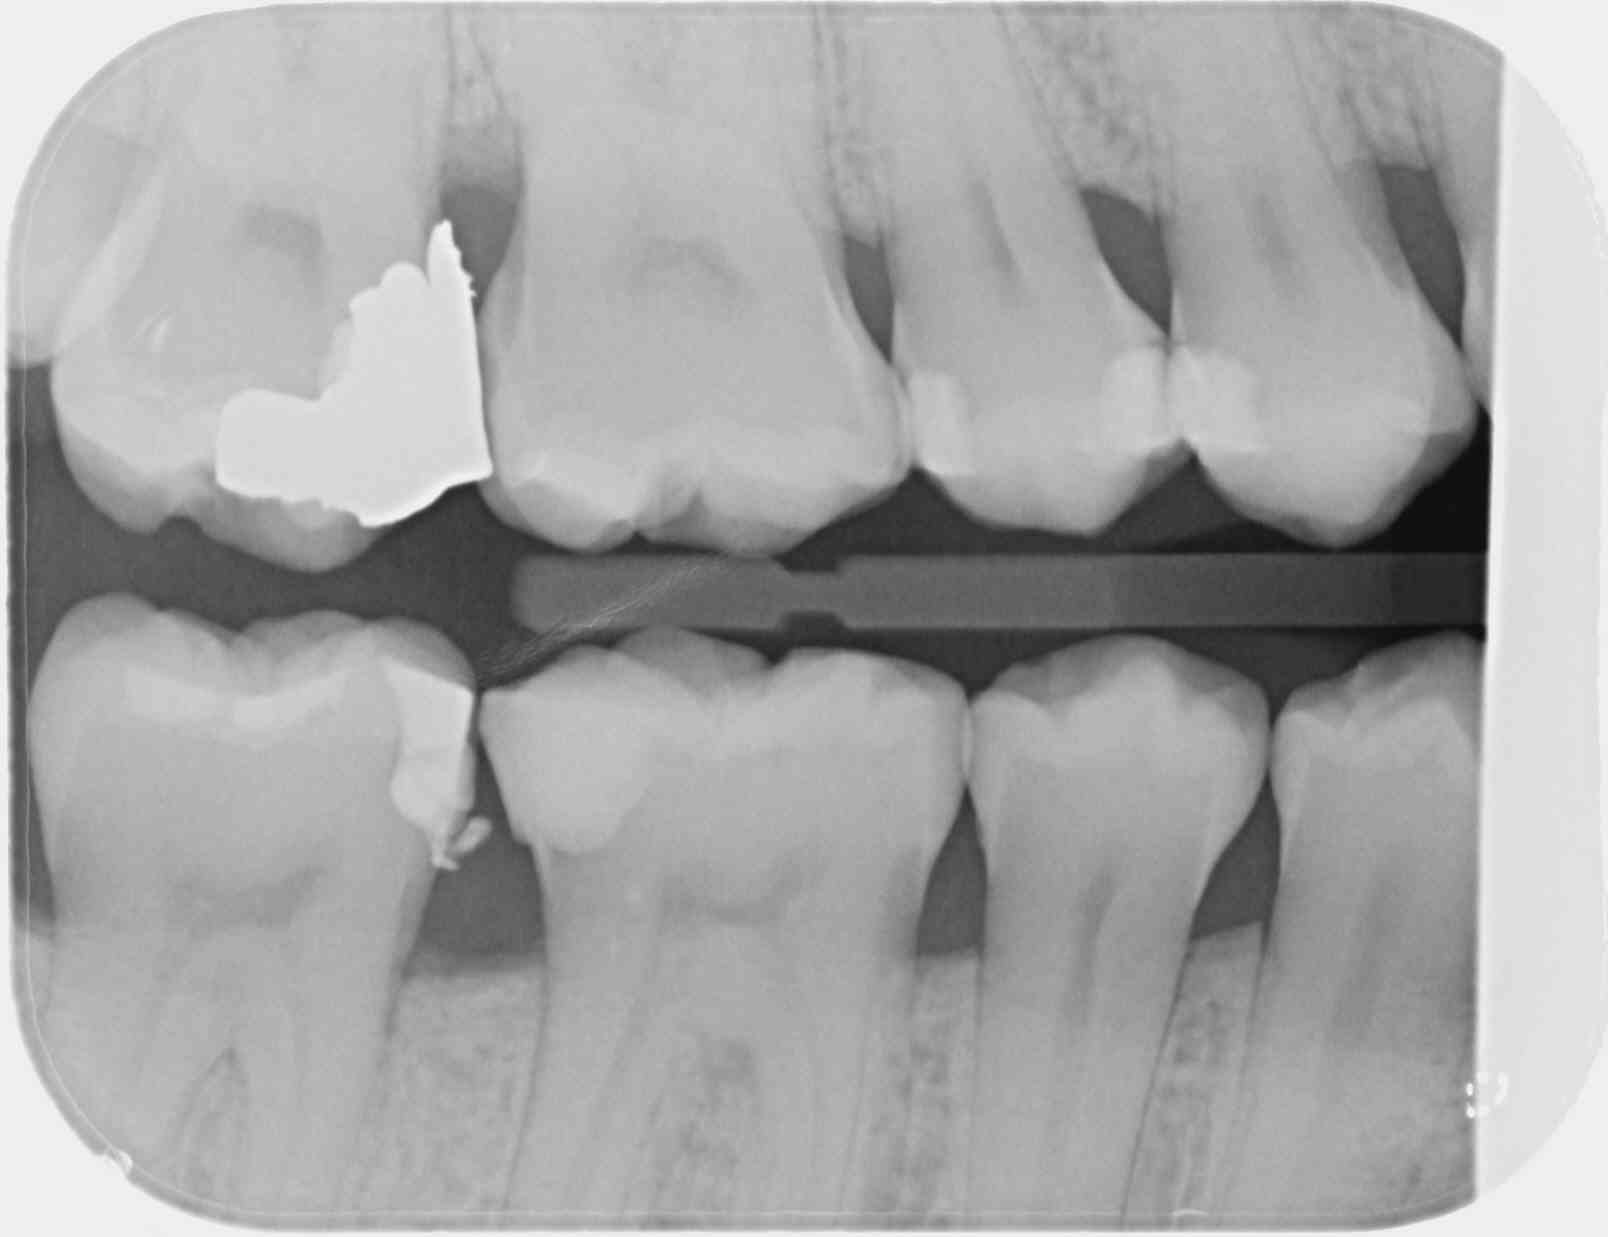

C'est une faille de la CCAM qui permet, avec un peu de mauvaise foi, de coder 4 secteurs avec seulement 2 clichés, le nombre de clichés n'étant pas précisé dans le libellé.

1 radio (au singulier) en bite-wing secteur 1 et 4 = 7.98€ (HBQK389, 2 secteurs mais 1 seul cliché)

2 radioS (au pluriel) en bite-wing secteurs 1, 2 , 3 et 4 = 31.92€ (HBQK443, 4 secteurs, plusieurs clichés sans précision sur leur nombre).

Certains trouvent qu'on joue avec le feu. Chez nous, les CDC n'ont rien trouvé à redire à ça.

Je considère que la nomenclature ne nous fait pas de cadeau, je ne lui en fais pas non plus.

T'es con d'utiliser des films taille 3 surtout avec des CDC de bonne composition. ca fait que 2 secteurs ou 4. Alors que 4 clichés ca fait 4 secteurs....ou 8. Les rétro alvéolaires sont offertes. -)

Allez un petit dernier pour la route : avec des taille 3 tu n'as pas forcément l'os alvéolaire bien visible et ça mon garçon c'est un indu. -))))